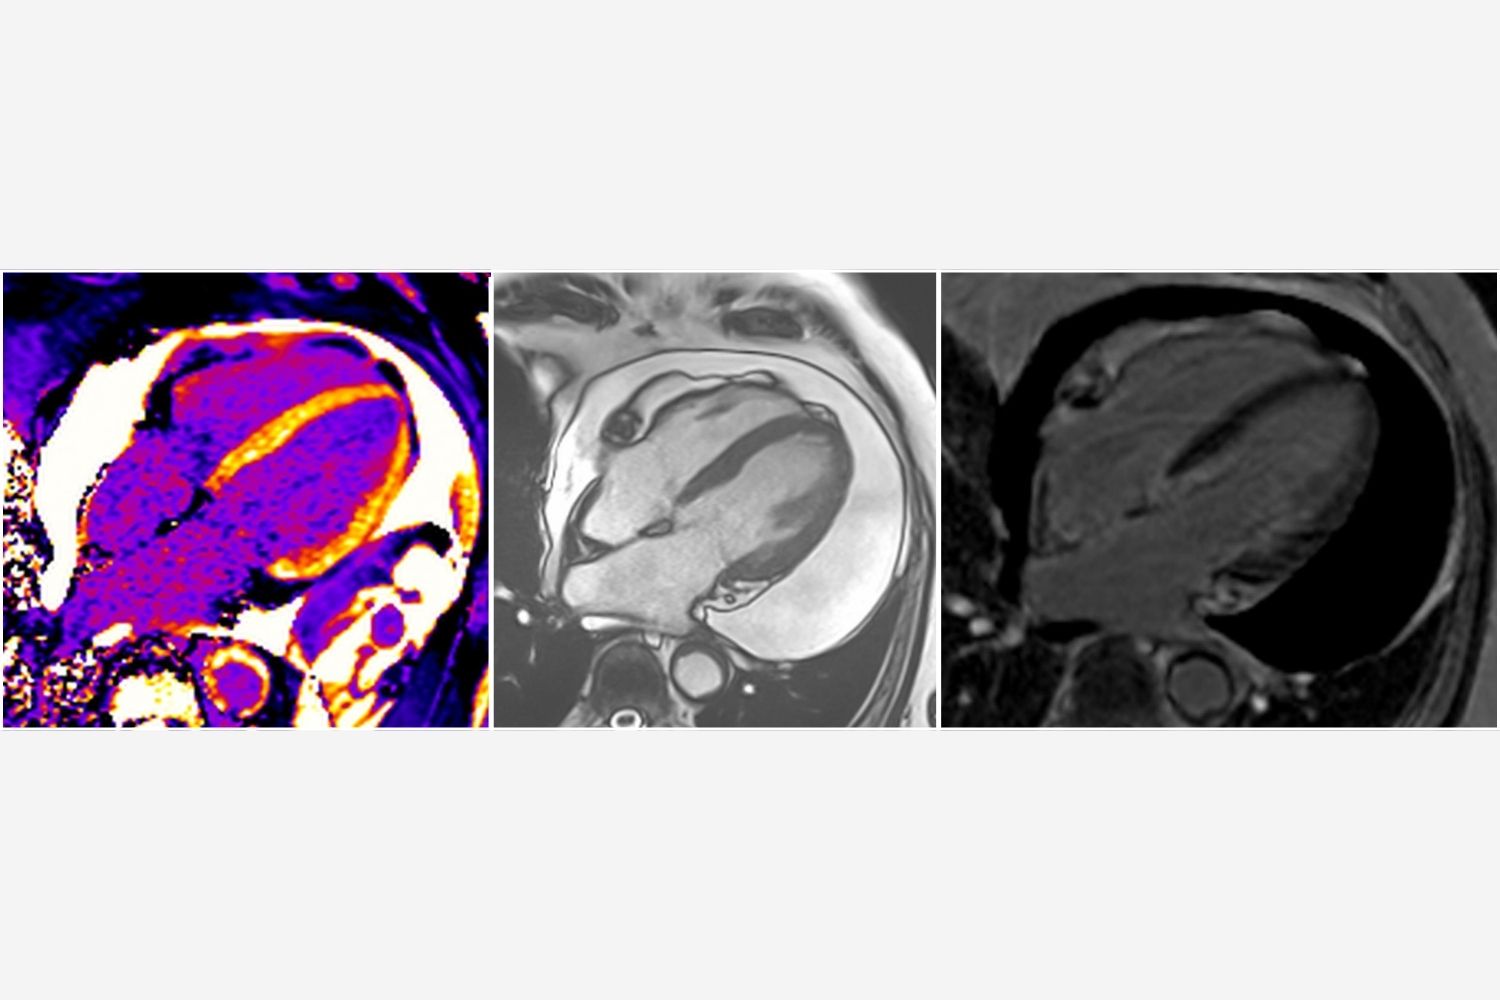

Image of the Week - 19 November 2025

Image of the week